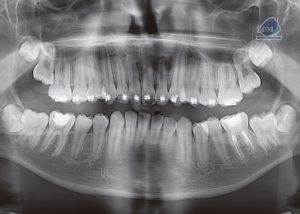

Paciente masculino de 17 años de edad, es referido al Instituto de Diagnóstico Maxilofacial – IDM para evaluación general.En la radiografía panorámica (Figura 1), se